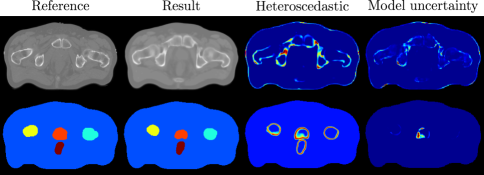

An example of the model output is shown in Fig 2. We calculated the Mean Absolute Error (MAE) between the predicted and reference scans across the body and at each organ (Tab. 1). The fuzzy DICE score between the probabilistic segmentation and the reference was calculated for the segmentation (Tab. 1). Best performance was in our presented method (M4) for the regression across all masks except at the bladder. Application of the multi-task heteroscedastic network with drop-out (M4) produced the most consistent synCT across all models with the lowest average MAE and the lowest variation across patients ( versus [1] and [5]). This was significant lower when compared to M1 () and M2 (). This was also observed at the bone, prostate and bladder (). Whilst differences at were not observed versus M2b and M3, the consistent lower MAE and standard deviation across patients in M4 demonstrates the added benefit of modelling heteroscedastic noise and the inductive transfer from the segmentation task. We performed better than the current state of the art in atlas propagation, which used both T1 and T2-weighted scans [1]. Despite equivalence with the state of the art (Tab. 1), we did not observe any significant differences between our model and the baselines despite an improvement in mean DICE at the prostate and rectum ( and ) versus the baseline M1 (, ). The intrinsic uncertainty (Fig. 2) models the uncertainty specific to the data and thus penalises regions of high error leading to an under-segmentation yet with higher confidence in the result.

The predictive uncertainty can be exploited for quality assurance (Fig. 4). There may be issues whereupon time differences have caused variations in bladder and rectum filling across MR and CT scans causing patient variability in the training data. This is exemplified by large errors in the synCT at the rectum (Fig. 4) and quantified by large localised z-scores (Fig. 4g), which correlate strongly with the intrinsic and parameter uncertainty across tasks (Fig. 2 and 4).